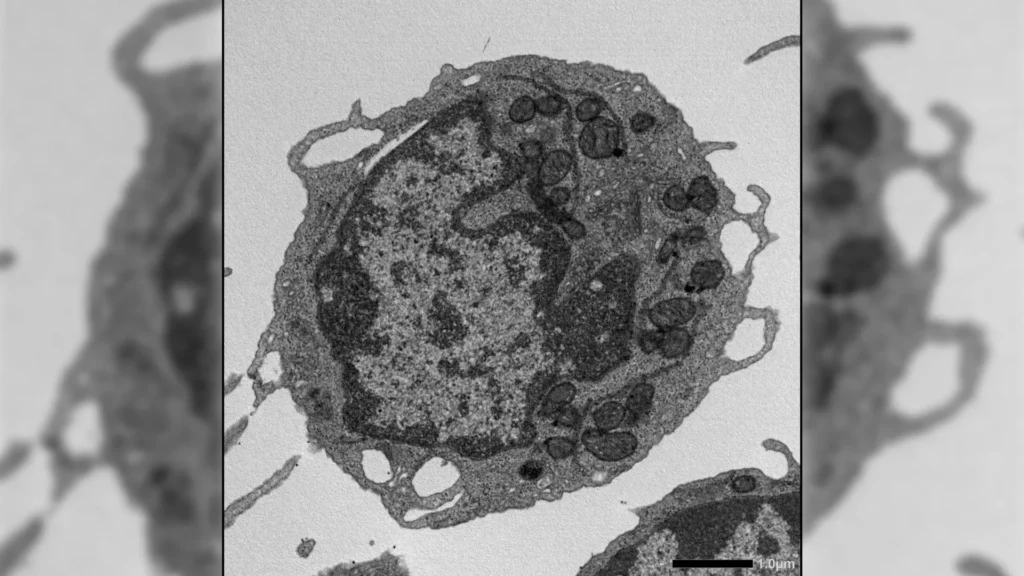

The mechanisms through which these specific fat distribution patterns exert their detrimental effects on the brain are complex and likely multifactorial. Chronic low-grade inflammation, a hallmark of excess adipose tissue, particularly visceral fat, is believed to play a central role. Adipocytes (fat cells) are not merely passive storage depots; they are metabolically active cells that secrete a variety of hormones and pro-inflammatory cytokines, which can cross the blood-brain barrier and contribute to neuroinflammation. Furthermore, insulin resistance, often associated with both high pancreatic fat and elevated visceral adiposity, can impair glucose metabolism in the brain, leading to energy deficits and neuronal dysfunction. Oxidative stress, altered lipid metabolism, and vascular dysfunction are also potential pathways through which these specific fat distributions could compromise brain integrity. Gray matter loss, a critical indicator of neuronal damage and atrophy, and accelerated brain aging, signify a decline in the brain’s structural and functional resilience, ultimately contributing to cognitive decline and increasing vulnerability to neurodegenerative conditions such as Alzheimer’s disease.